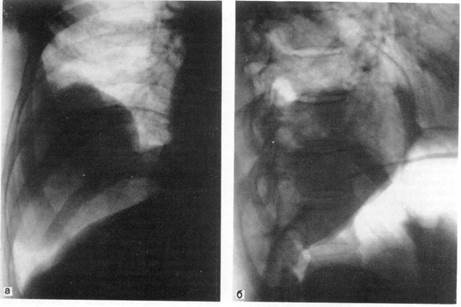

Показанием к введению воздуха или кислорода в брюшную полость с последующим рентгенологическим обследованием являются образования, прилежащие к нижним долям легких и куполу диафрагмы, когда не удается ответить на вопрос: располагаются ли они в легком, исходят из диафрагмы или находятся в под диафрагмальном пространстве, например в печени (рис. 4).

Методика наложения пневмоперитонеума состоит в следующем. В положении больного на спине в точке, располагающейся на 2—3 см выше и левее пупка, на всю глубину брюшной стенки выполняется послойная местная анестезия. В момент прокола париетальной брюшины появляется ощущение свободного, без сопротивления вытекания обезболивающего раствора из шприца даже при отсутствии давления на поршень. После этого иглу присоединяют к пневмотораксному аппарату и в брюшную полость дозированно в течение 3—5 мин вводят 1000—1200 мл кислорода, воздуха или закиси азота. Последний удобен ввиду быстрого рассасывания и некоторого анальгезирующего эффекта. Больному на 20—30 мин придается положение на здоровом боку с несколько приподнятой верхней частью туловища. При этом введенный газ перемещается под купол диафрагмы, оттесняя его кверху. На рентгенограммах удается четко дифференцировать нижнюю поверхность диафрагмы. В удалении газа из брюшной полости необходимости нет. В течение 3 — 8 сут ок воздух рассасывается самостоятельно. Кислород и закись азота исчезают раньше, обычно к исходу первых суток.

Рис. 4. Доброкачественная опухоль правого легкого в условиях искусственного пневмоперитонеума.

а — прямая рентгенограмма; б — боковая рентгенограмма.